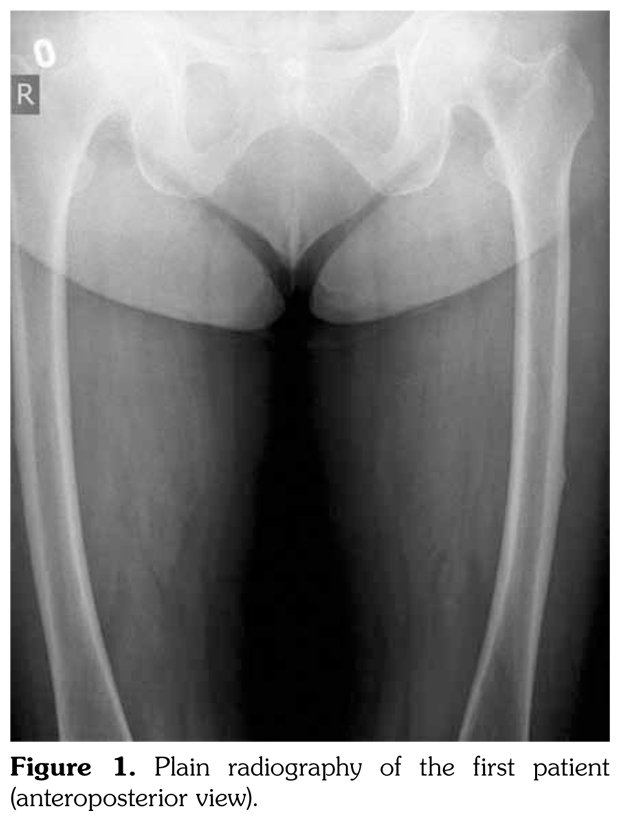

Case 1– A 73-year-old female patient presented with low back, knee, and anterior thigh pain. Pain severity was 8 over 10 point according to visual analog scale. She had difficulty in walking because of pain. She had a history of arthroscopic knee surgery for meniscal pathology in her left knee five years ago. She had chronic low back pain due to L4-5 disc herniation and lumbar spinal stenosis. She had been treated for osteoporosis with alendronate for two years, then with salmon calcitonin for two years and ibandronic acid for a year. Neurological examination was normal. Plain radiographs revealed bilateral lateral cortical thickening in the femur (Figure 1). Magnetic resonance imaging was done to rule out fracture. Bone scintigraphy showed increased uptake in bilateral femoral diaphysis. Routine biochemical tests were normal except increased urinary deoxypyridinoline. Urinary deoxypyridinoline level was 63 nM/mMCre (normal range: 3-7.4 nM/mMCre).

Case 2– A 61-year-old female patient presented with anterior thigh pain and difficulty in walking. Pain severity was 7 over 10 point according to visual analog scale. She had been treated with alendronate 70 mg per week with calcium plus vitamin D for two years. Plain radiographs of femur were taken upon clinical presentation. Cortical stress reaction was detected in both femoral shafts on plain radiographs (Figure 2). Computed tomographic imaging was performed to rule out fracture (Figure 3). Bone scintigraphy showed increased uptake in distal (1)/3 ends of femoral shafts (Figure 4). Serum calcium value was normal and urinary deoxypiridinoline level was mildly increased (46 nM/mMCre).

Bone scintigraphy of the patients revealed increased uptake in femoral diaphysis. Atypical bisphosphonate associated subtrochanteric and femoral shaft stress fractures show specific appearance on bone scintigraphy characterized by mild uptake in multifocal endosteal thickening of the lateral femoral diaphysis.(11)